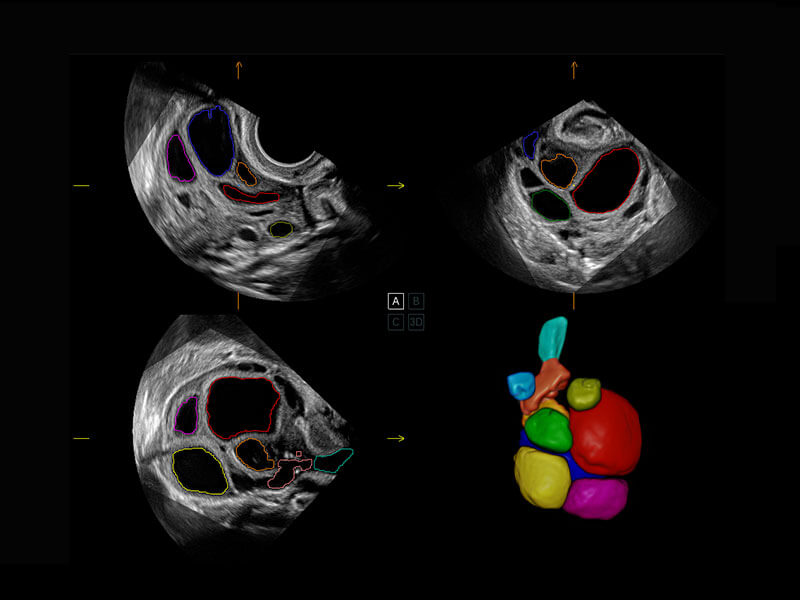

胎心容积成像

P60提供简单易学易用的高端诊断工具,为您中晚孕筛查提供快速清晰的解剖信息。

S-Fetus能够助您在实时扫查过程中自动识别标准切面、自动测量并录入报告。一个按键,即可快速、高效地获取胎儿生理指标,简化您的产科检查操作。